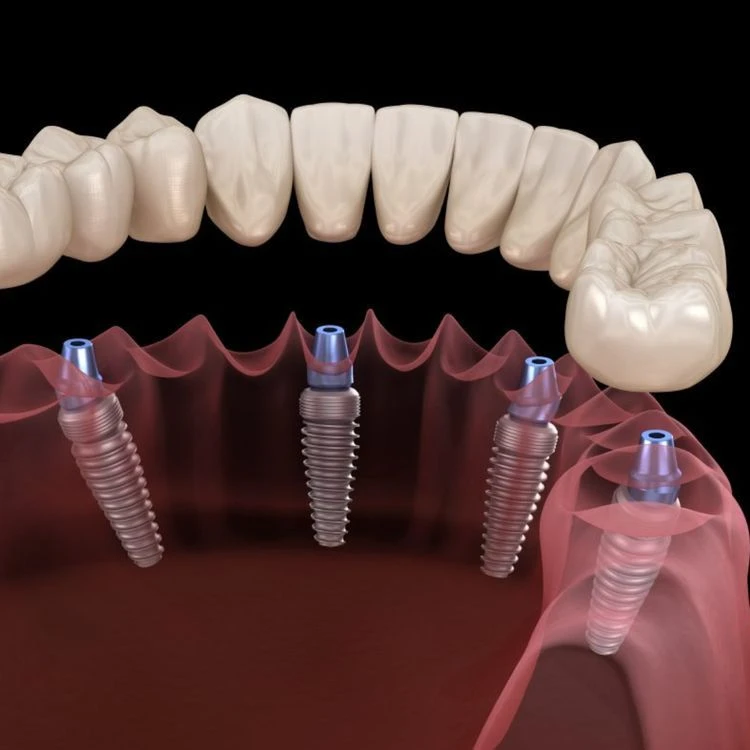

All-on-4 implant tedavisi, tüm dişlerinizi tek seans içerisinde çıkartılıp yerine 4 adet implant üzerine sabitlenen bir köprü ile değiştirmektir. Bu tedavi yöntemi, diş eksiklikleri olan kişilere daha hızlı ve daha kolay bir diş restorasyonu sağlar.

All-on-4 implant tedavisi, bir cerrahi işlemle yapılır. Tedavi sırasında, öncelikle diş etleri kaldırılır ve dişler çekilir. Sonrasında, implantlar çene kemiğine yerleştirilir ve geçici bir köprü takılır. Yerleştirilen implantlar iyileşme sürecinde kemikle kaynaşır ve kalıcı köprü yerleştirilir.